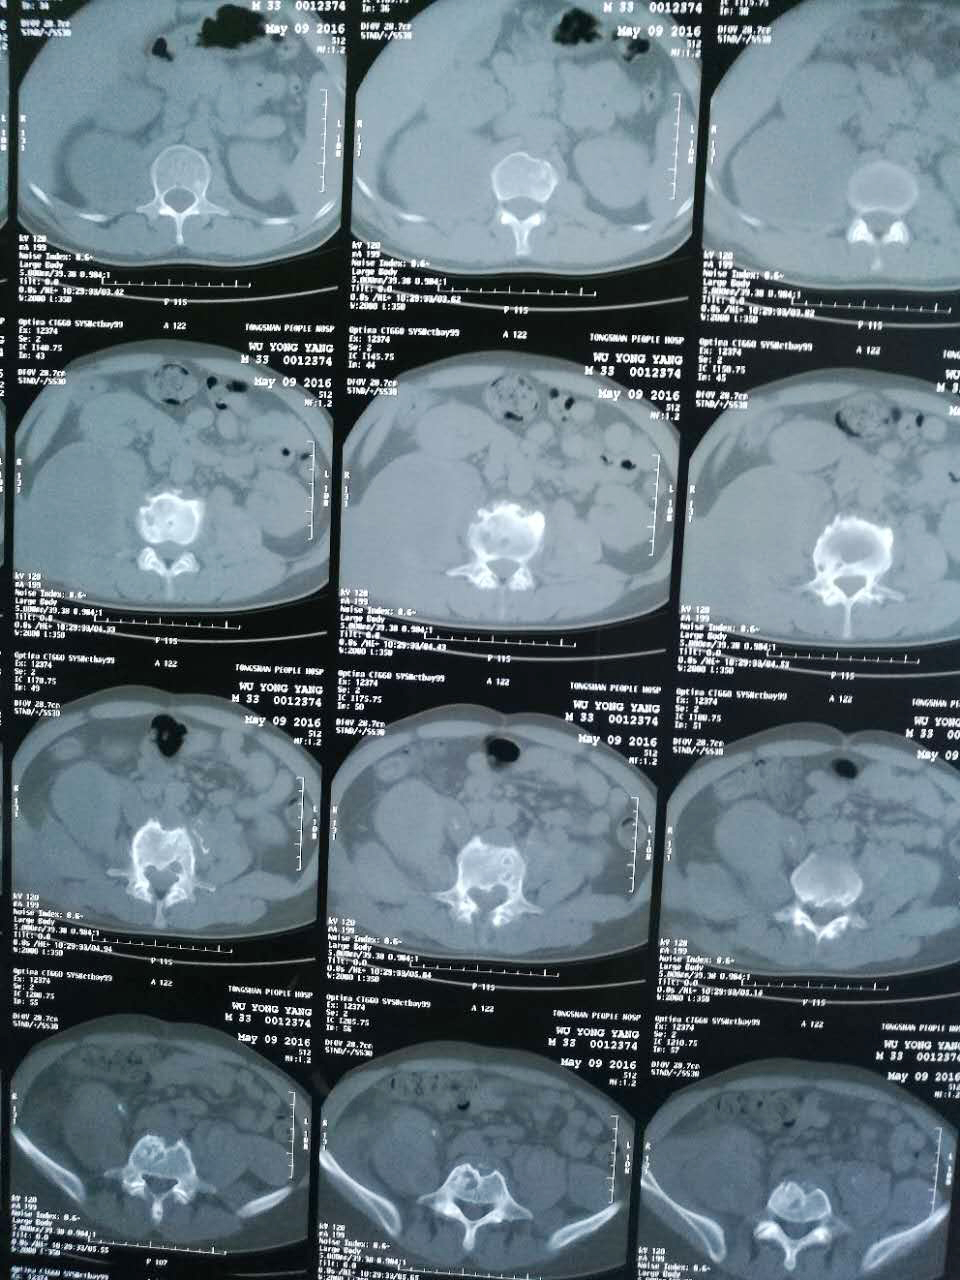

腰椎结核一般在发病时,患者会出现低热、疲倦、消瘦、盗汗、食欲不振与贫血等全身症状。儿童常有夜啼,呆滞或性情急躁等。随着病情的发展,不少患者会出现疼痛加重呈放射性疼痛,沿神经传播到下肢、肩部、臀部等。腰椎结核发病严重,椎体出现破坏,患者会出现畸形,脊柱多有后凸,患者不能弯腰、也不能直腰行走。

湖北夏小中医院专家表示:腰椎结核截瘫是其严重的并发症。有资料显示:它占了所有脊椎结核的10%~20%。白求恩医科大学报导950例脊柱结核,其中有36.8%并发截瘫,可见腰椎结核合并截瘫,相当多见,是危害我国人民健康的常见疾病,治疗上防止截瘫已刻不容缓。>>>腰椎结核好治吗?

我院治疗骨结核属于中医保守治疗,不提倡手术治疗,可根据病情有选择性停止抗结核药物,以专属药物透皮在病患区形成高浓度侵润,直接穿透性杀死结核菌,其提脓拔毒功效以自身的体液为载体引流脓肿,排出炎性物质,消除肿胀,使开胃健脾,促进食欲,固五脏之本,从而增强了机体的抗病能力,外治透皮吸收,有效的激活免疫巨噬细胞吞噬杀灭不同酸碱环境及不同部位的结核菌,改变了患部的酸性环境使患部具有生理性的防御、自稳和监护的能力,创建一个不适宜结核菌发展的生态环境,结核菌自然就会消失,患部有了自稳、自我修复的生理条件,达到彻底治疗骨结核的目的。避免了西医对于骨与关节结核性疾病的无奈,被迫采取截肢的治疗骨结核方式对病人造成的肢体损伤和精神的痛苦。